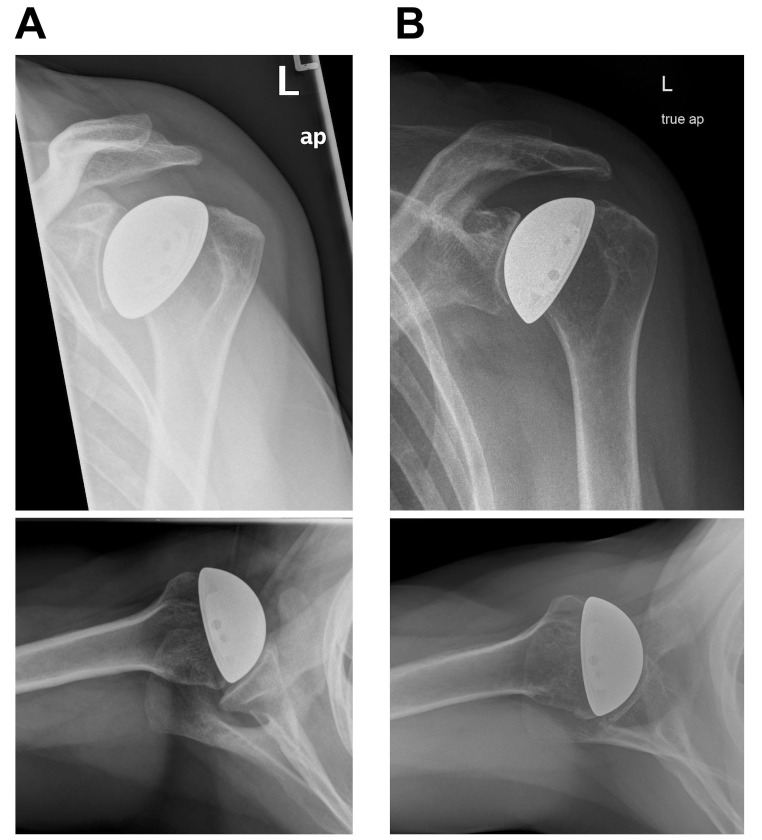

Results: Seventeen shoulders were retrospectively included in the implant survival analysis. Two patients underwent revision surgery. five patients died with the implant and were therefore censored. Cumulative survival rate was 100% after ten years and 93.3% after 15 years. Seven shoulders were available for clinical and radiological evaluation at a mean follow-up of 19 years (range 17-22 years). Age- and sex-adjusted CMS improved from preoperative to the latest follow-up (44.4% vs. 82.9%; p < 0.01). No glenoid erosion of higher degree (Sperling grade > 2) and no signs of implant loosening were observed. All patients had Walch type A glenoids preoperatively.